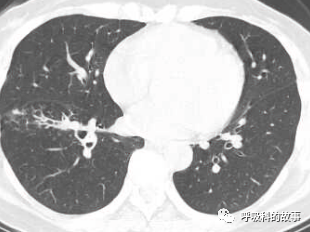

1個月前,黃女士來到了杭州市第一人民醫院呼吸科,找到我看病,我給她複查了肺部CT,如下:

初一看,好像就是普通的肺炎,可是為什麼相隔兩個月在同一部位反覆發生呢?另外,右下葉肺門較左側明顯增大,感覺到管腔似乎也不是那麼清爽,於是我繼續開啟縱隔窗繼續檢視影像情況。

這一看嚇我一跳,患者右下葉支氣管腔內有高密度影,這讓我首先想到的就是支氣管異物堵塞管腔,從而引起阻塞性肺炎。於是我在認真檢視後,嚴肅地對患者說要住院。黃女士可能一來工作繁忙,二來對我的診斷可能表示懷疑,因為她記憶裡沒有誤吸的事件發生,三來以前的CT報告也沒有提示支氣管異物,於是要求繼續口服藥物治療。